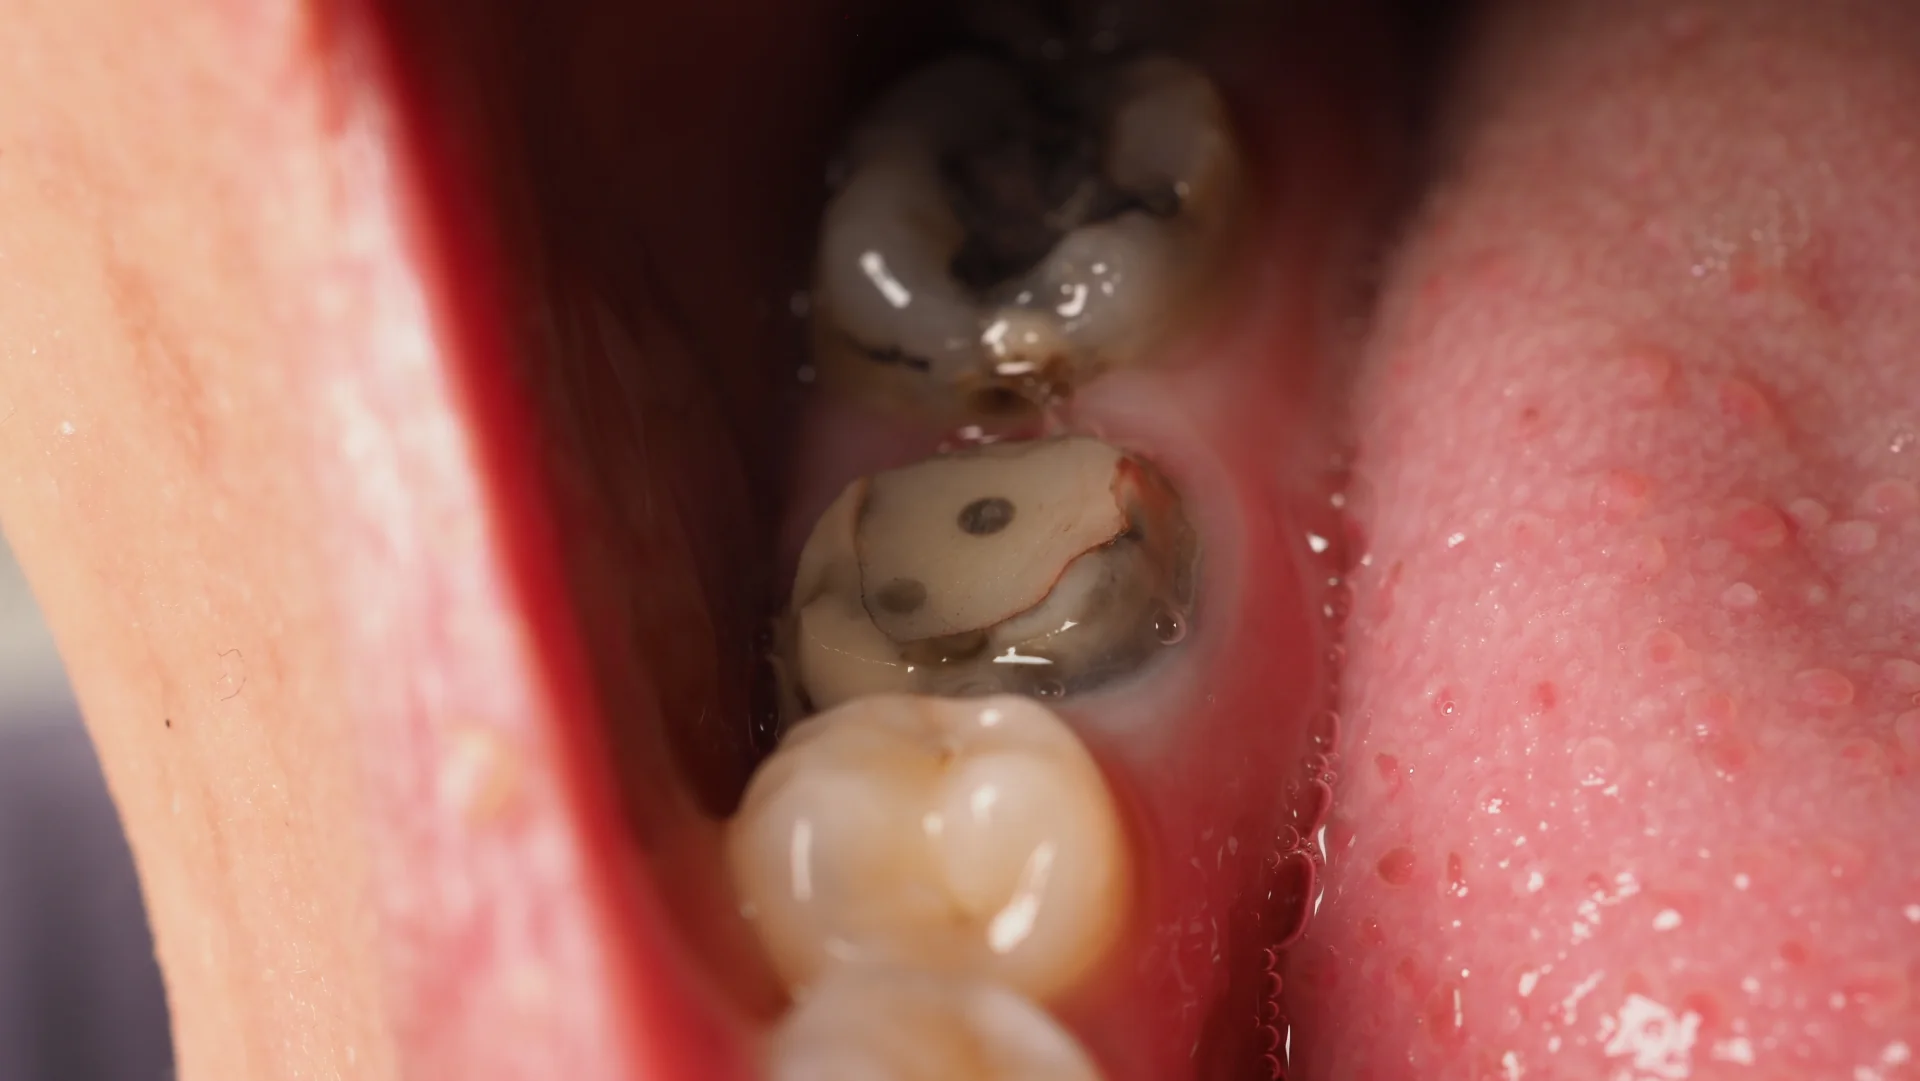

Die Bakterien erreichen das Zahnbein (Dentin). Dieses ist weicher als Schmelz, daher breitet sich Karies hier schneller aus. Jetzt treten oft Zahnschmerzen, Empfindlichkeit und sichtbare Verfärbungen auf.

Die Karies dringt bis ins Zahnmark (Pulpa) vor. Es kommt zu einer Entzündung, die starke Schmerzen verursacht. Häufig ist eine Wurzelbehandlung notwendig, um den Zahn zu retten.

Wird die Karies nicht behandelt, kann sich die Entzündung ausbreiten, bis zur Zerstörung des Zahns. In diesem Stadium bleibt oft nur die Zahnextraktion. Um die entstandene Lücke im Gebiss zu schließen, ist ein Zahnersatz notwendig.

Karies zeigt sich in frühen Stadien oft als weiße oder bräunliche Flecken auf dem Zahnschmelz – sogenannte „white spots“. Mit Fortschreiten der Erkrankung entstehen sichtbare Verfärbungen, dunkle Stellen oder ein Loch im Zahn. In schwereren Fällen ist die Oberfläche weich, rau oder eingestürzt. Da viele Veränderungen schmerzfrei bleiben, hilft eine zahnärztliche Kontrolle, Karies frühzeitig zu erkennen, auch wenn sie äußerlich noch kaum sichtbar ist.